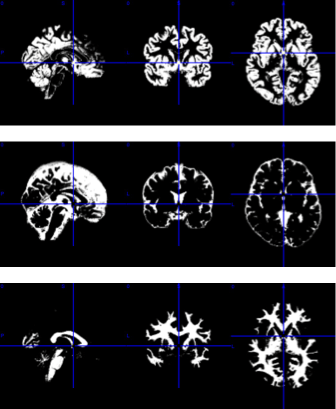

Structural MRI is a non-invasive imaging technique that provides detailed visualization of brain anatomy and detect structural lesions or abnormalities. It characterizes brain structure, focusing on detecting associated structural abnormalities like tumors, stroke, or degenerative changes, but does not directly assess functional dynamics. It serves as an anatomical reference for other functional and advanced techniques like fMRI and DTI. This is crucial for diagnosing neurological disorders, tracking disease progression, and understanding the impact of various conditions on brain structure.

Image processing and analyses are predominantly conducted using MATLAB and Python. External plugins, including SPM25 and CAT12, facilitate the preprocessing of sMRI, fMRI, and PET images. The preprocessing pipeline encompasses segmentation, slice timing correction, motion correction, coregistration, normalization, and smoothing. FSL, a Python-based library, assists in the preprocessing and analysis of dMRI and fMRI. Additionally, MRIcron is employed for image visualization and comparison.

Statistical analyses are employed to compare group differences. Structural differences are assessed using voxel-based morphometry, surface-based morphometry, and deformation-based morphometry. Functional differences are measured through seed-based correlation analysis and independent component analysis. Diffusion tract measurements are compared via tract-based spatial statistics and voxelwise statistics. PET images are analyzed using standard uptake value measurements.

In this stage, images are processed for motion correction, denoising, smoothing, modulation, and alignment between modalities

Structural MRI